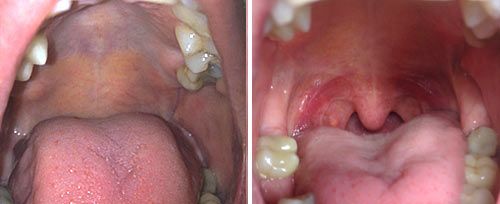

Clinical Results